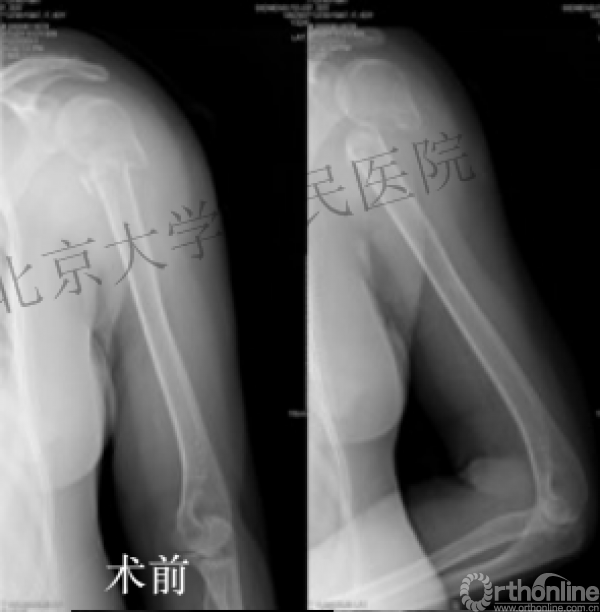

内侧皮质粉碎,低位外科颈骨折,肱骨头-干角维持困难。

术后复位丢失,肱骨头内翻畸形。

能否该偏心固定(钢板)为髓内固定,增加力臂?

早知今日,何必当初?

此时对比髓内钉是不是有很大优势?